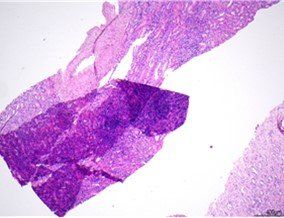

H&E - BMT Scheme

This is an excellent preparation of a BMT biopsy, with balanced H&E staining, good chromatin detail, and selective staining of cell types within the bone marrow tissue. This slide was scored 9/10 at assessment.